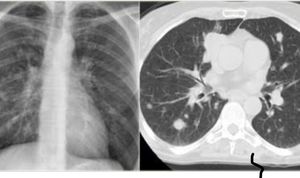

Midiastinal lymphaedenopathy

Mediastinal and hilar lymphadenopathy suggestive of Tuberculosis.

Sarcoid vs tuberculas

Pulmonary tb with mediastinal lymphadenopathy? There is cavity(tb lesion) in apex of right lung